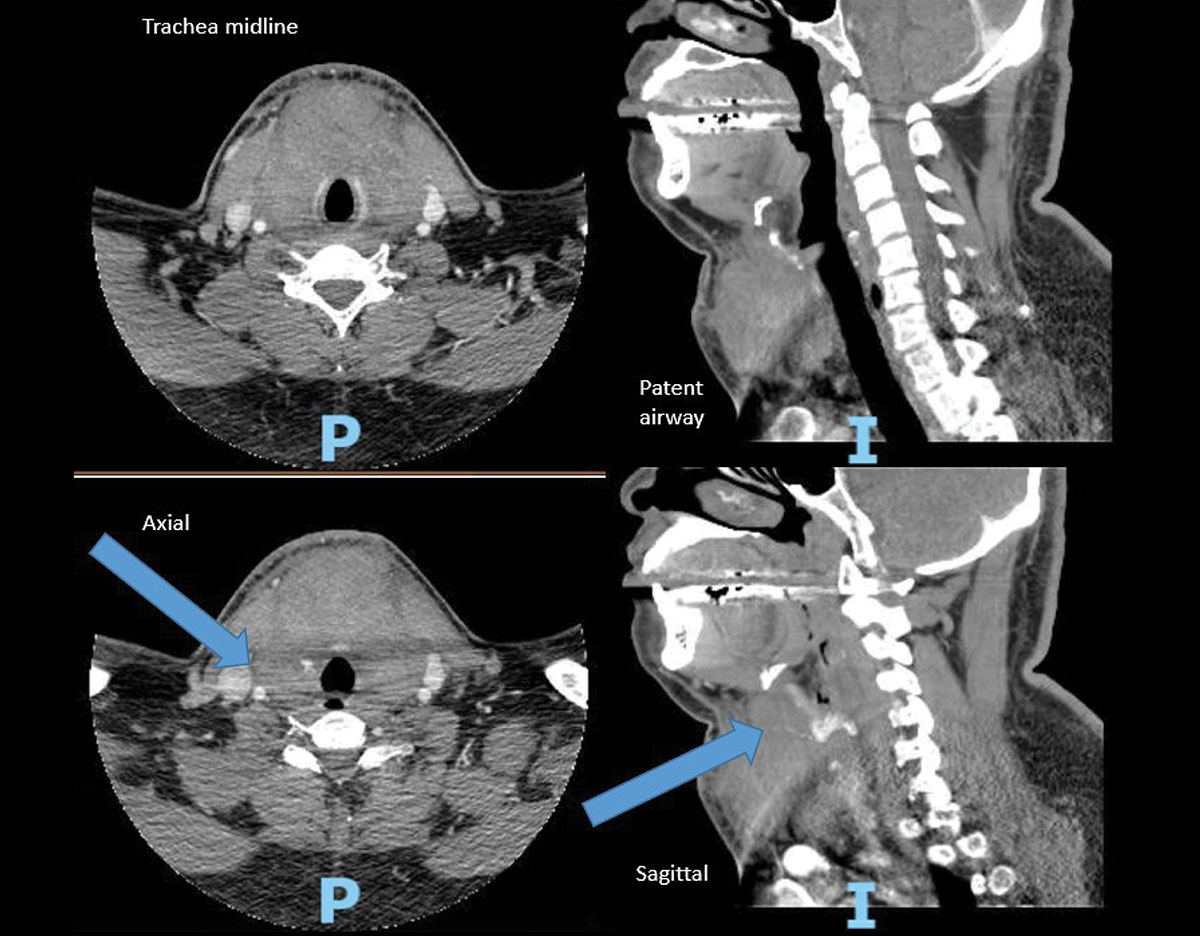

Postoperative Anterior Neck Hematoma (ANH) Timely Intervention is

Postoperative Anterior Neck Hematoma (ANH) Timely Intervention is Local Anesthesia Hematoma Hematoma is the effusion of the blood from the vessels, due to any injury or puncture mainly during the administration of. Comparing the use of local anesthesia with sedation with general anesthesia in the. Drilling and drainage is the main treatment for chronic subdural hematoma (csdh). Chronic subdural hematoma drainage under local anesthesia with sedation versus general anesthesia and its. Local Anesthesia Hematoma.